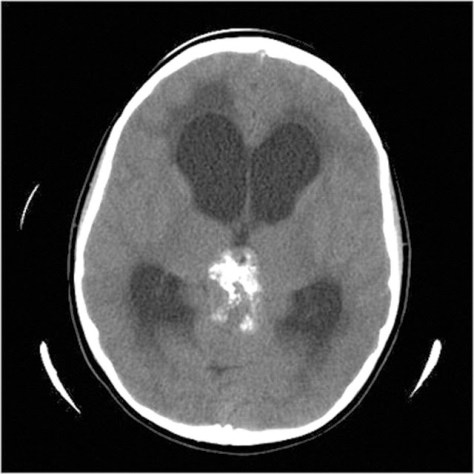

Clearly, MS is associated with pineal calcification. For example, one study showed 100 percent of individuals with MS who were consecutively admitted to a hospital had pineal calcification compared to only 43 percent for similar-aged controls with other neurological disorders. In addition, groups who have a low MS incidence (e.g., African Americans, Japanese) also have less pineal calcification. Fluoride may affect the enzymatic conversion of tryptophan to melatonin. Fluoride may also affect the synthesis of melatonin precursors (e.g., serotonin), or other pineal products (e.g., 5-methoxytryptamine). The human pineal gland contains the highest concentration of fluoride in the body. Whether or not fluoride interferes with pineal function in humans requires further investigation.